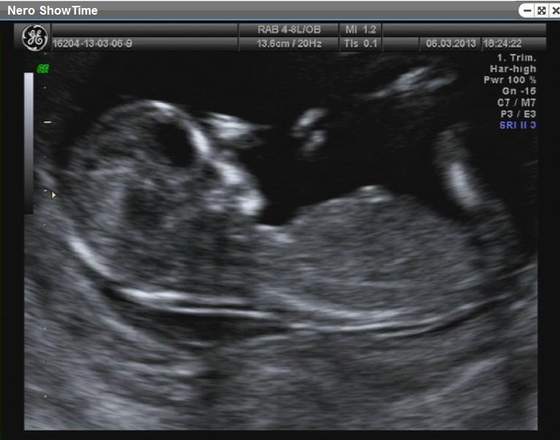

mika tak, według poprzedniego usg wczoraj miałam dokładnie ukończony 13tc, a wczorajsze usg podało, że 13t1d, no ale wahanie parudniowe może być

No już tak na prawdę w 9tc masz ludka z ręcami i nogami hi hi ale teraz to już jak prawdziwi człowieczek wygląda. Jeszcze 2 tyg temu wyglądał bardziej jak ufo

przezierność 1,44 kość nosowa obecna, powiedział, że wszystko jest w porządku. Nie mam takiego cudnego filmiku jak z Misią (ona się ślicznie pokazywała) ale jest. Chyba się później dodatkowo jeszcze gdzieś wybiorę. Płci jeszcze nie znamy, a pamiętam jak Misia się pokazała na początku właśnie tego badania pierwsze co to pupe pokazała